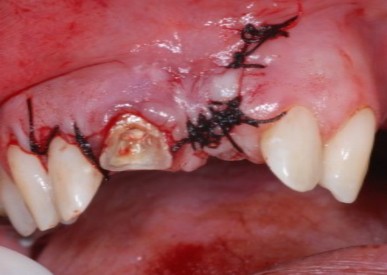

- Figura 17 – Sutura com fio de seda 4.0.